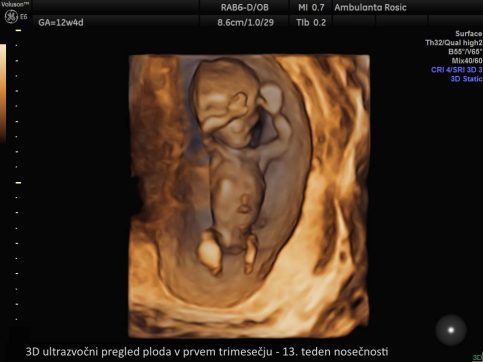

3D/4D ultrazvočni pregled ploda

Bodoči starši želite čimprej spoznati svojega malčka. To nam omogoča 3D/4D ultrazvočni pregled ploda, pri katerem z našim vrhunskim ultrazvočnim aparatom posnamemo 3D sliko ploda, četrta dimenzija (4D) pa doda še gibanje.

S pregledom opazujemo plodov razvoj, gibanje, pogledamo obraz in vam s tem omogočimo čustveno povezavo z otrokom.

V prvem trimesečju lahko 3D/4D ultrazvočni pregled ploda opravimo ob prvem pregledu ali hkrati z meritvijo nuhalne svetline. Pri 3D/4D ultrazvoku v drugem in tretjem trimesečju nosečnosti določimo tudi lego ploda, položaj posteljice, količino plodovnice, preverimo rast in telesno težo ploda, izmerimo pa lahko tudi pretoke skozi popkovnične žile z Dopplersko ultrazvočno preiskavo za oceno stanja ploda. 3D/4D ultrazvok ploda lahko opravimo tudi ob morfologiji ploda.

3D/4D ultrazvok v nosečnosti izvajamo z vaginalnim (nožničnim) ali abdominalnim (trebušnim) tipalom. Vaginalno tipalo uporabljamo pri ultrazvočni preiskavi v prvem trimesečju, abdominalno tipalo pa v drugem in tretjem trimesečju nosečnosti. S tem imate pri nas nosečnice možnost opraviti 3D/4D ultrazvok ploda že od prvega pregleda v nosečnosti dalje.